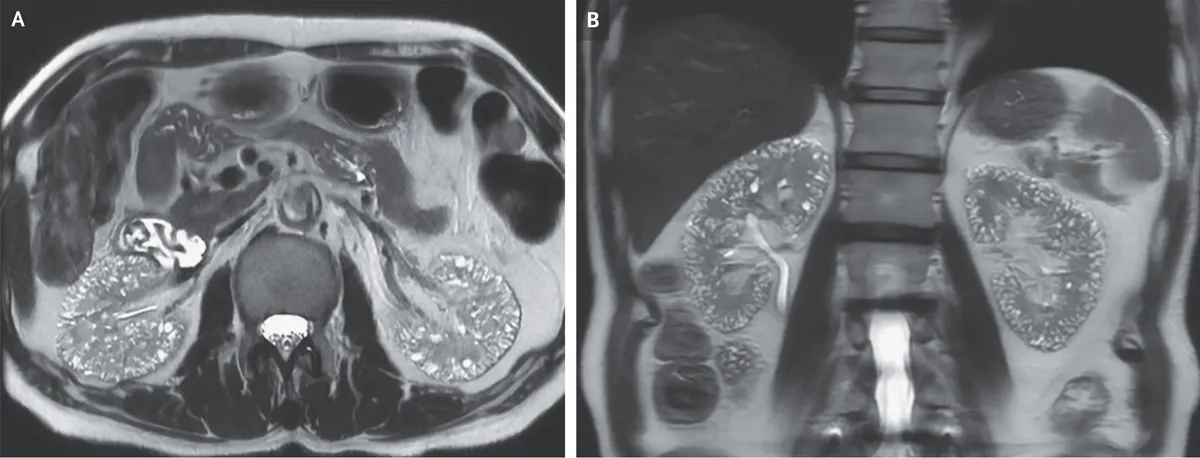

Microcistos renais e lítio: existe relação?